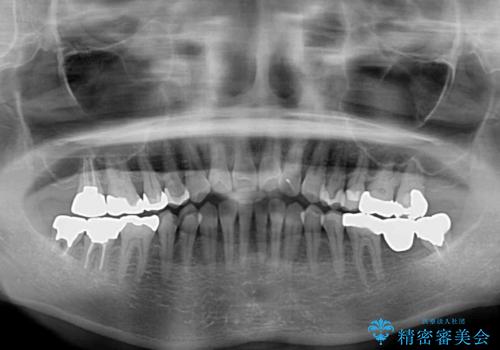

前歯の突出感と上下の隙間 インビザラインによる矯正治療

- 前歯の上下スペースと前歯の隙間を気にして来院された患者様です。

インビザラインにより上下の前歯の隙間を閉じながら、IPRを用いて口元の突出感を合わせて改善していくこととしました。

上下の隙間に舌が入り込むことが、すきっ歯やオープンバイトの原因であったため、舌の筋肉のトレーニングも並行して行い、後戻りの抑制を図りました。